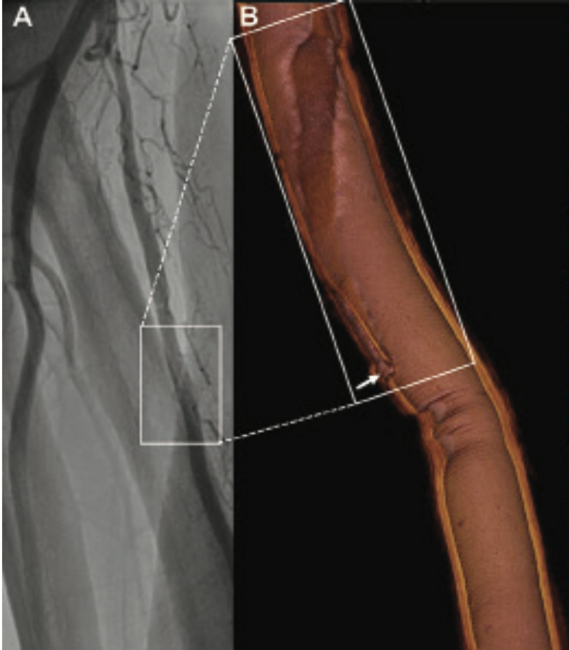

Radial Artery Spiral Dissection Confirmed by OCT Without Guidewire Shadow

A 75-year-old man underwent right transradial coronary angiography because of acute myocardial infarction. Postprocedural radial angiography revealed a dissection with a spiral luminal filling defect in the proximal radial artery, corresponding to a National Heart, Lung, and Blood Institute type D dissection (Figure 1A; Video 1). In order to acquire a full, 360° optical coherence tomography (OCT) image, we withdrew the guidewire out of the sheath ahead of pullback and left the OCT imaging wire in the vessel alone. However, subsequent pullbacks were performed without any difficulties. Without the guidewire shadow, it was clear that the dissection started from a disruption of an intimomedial membrane (Figure 1K), which was outlined perfectly as a so-called “barbershop pole” by three-dimensional OCT (Figure 1B; Video 2). The false lumen extended along the long axis of the vessel (Figure 1G) by rotating clockwise from 7 o’clock to 4 o’clock at cross-sectional images (Figures 1C to 1K).